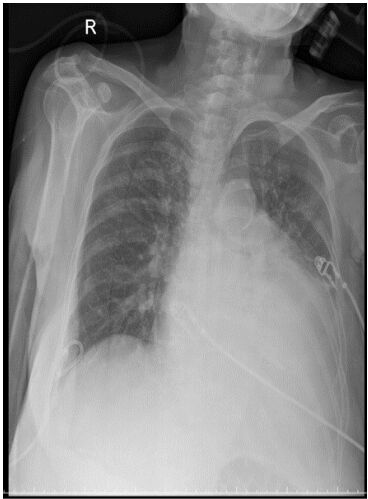

4. 病人是位29歲男性電子工程師派駐中國深圳,三個星期來,時有間歇性發燒及逐漸性呼吸困難,先在深圳 門診求醫,初以為一般感冒治療,後以支氣管炎診斷治療罔效,乃急回台灣求醫。經檢查,意識: E4M6V5; BP: 122/75 mmHg; PR: 116/min; RR: 21/min; Temperature: 37.6℃; SPO2: 94%(room air) 頸靜脈不怒張,未有貧血,胸部呈現瀰漫性濁音,心臟擴大,有Grade III/VI Diastolic murmurs at left upper sternal border,無肝脾腫大,無腹水。皮膚未有紅腫或出血斑點。2016/12/23心電圖及胸部X光如 圖。其血液、尿液及生化如次:Hemograms: WBC, 13.54(k/uL); RBC, 4.74(M/uL); Hb, 13.0 (gm%); HCT,40.2(%); MCV, 84.8 (fL); MCH,27.4(pg); Platelet,329 (k/uL); Seg, 81.5(%); Eos, 0.2(%)。尿檢: 正常。請 問這位年青病人的最可能診斷是:

(A) Acute heart failure with lungs infection。 (B) Acute pericarditis。 (C) Acute viral myocarditis。 (D) Acute infective endocarditis。 (E) Acute pulmonary thromboembolism。